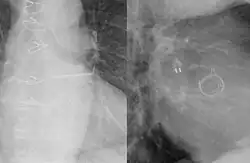

Die Implantation des Vorhofohrverschlusses erfolgt in einem Herzkatheterlabor unter tiefer Sedierung und bei lokaler Betäubung. Dabei wird die Leistenvene punktiert und nach transseptaler Punktion der Vorhofohrverschluss über einen Katheter im linken Vorhofohr platziert und entfaltet. Kontrolliert wird dies mittels Durchleuchtung und transösophagealer Echokardiographie (TEE).